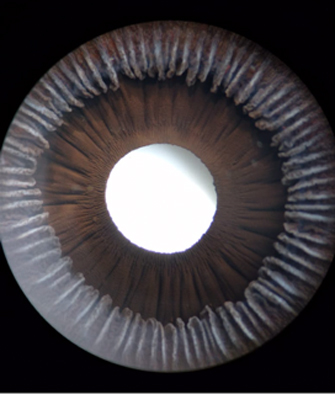

En la cara Posterior se ven pliegues radiales muy finos que se extienden desde el margen pupilar hasta el collarete ( miden ± 1.0 mm), y son conocidos como Pliegues radiales de contracción de Schwalbe. Existen ademas los llamados Pliegues estructurales de Schwalbe que son mas gruesos y mas distanciados en la porción ciliar de la cara posterior

Cara posterior de Iris: incluye Iris y Cuerpo Ciliar, Foto tomada de globo ocular de banco de ojos.